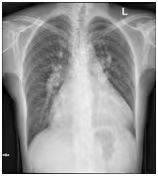

(图1)先天性心脏病患者(女,41岁)18F-FDG PET/CT显像图。1A.全身最大密度投影图示心脏明显扩大,房室各壁糖代谢明显增高;2B.心脏断层显像示各室壁糖代谢明显增高,SUVmax为11.5;1C.横断面、冠状面、矢状面三个不同层面示心腔明显增大,各室壁糖代谢明显增高。图2同一患者胸片。2A.2022年10月(手术前)胸片:心胸比为0.88;2B.2022年12月(手术后)胸片:心胸比例为0.76。